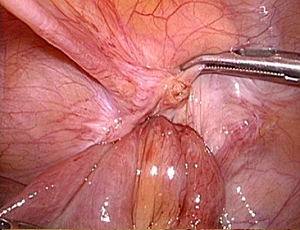

���`�ɂP�Omm�̌��������ē����������Ȃ��̒��ɑ}�����A���ǂɊJ�������i�w���j�A��j���m�F���A���b�V���V�[�g�����ɂ��Ăĕ����܂��B

�����ɂ͂Q�`�R�̂Tmm���x�̏����Ȍ��������Ď�p�{�s���܂����A�����͎�p��A���Ԃ��o�ĂقƂ�ǖڗ����Ȃ��Ȃ�܂��B